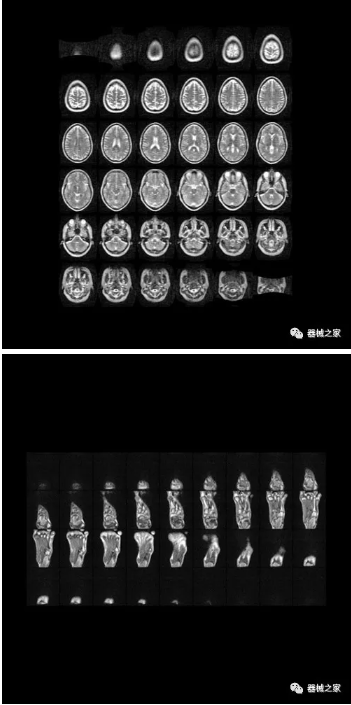

来看看这台便携式MRI 扫查出来的图像如何:

研发人员表示,该便携式MRI对于婴幼儿的成像,以及对手、肘、膝盖和脚等身体部位的成像非常有价值,此外,它的出现可以将磁共振成像技术带到一些资源匮乏、严重缺乏专业影像医生的农村或者是山区,其操作流程非常简单,图像出来后可以通过远程影像传输给大医院的影像专家来帮助诊断。